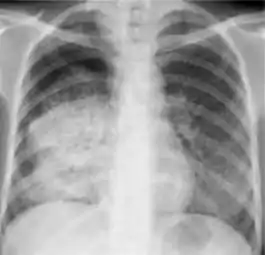

Tuberculosis creates cavities visible in x-rays like this one in the patient's right upper lobe.

A posterior-anterior (PA) chest X-ray is the standard view used; other views (lateral or lordotic) or CT scans may be necessary.

In active pulmonary TB, infiltrates or consolidations and/or cavities are often seen in the upper lungs with or without mediastinal or hilar lymphadenopathy.[1] However, lesions may appear anywhere in the lungs. In HIV and other immunosuppressed persons, any abnormality may indicate TB or the chest X-ray may even appear entirely normal.[1]